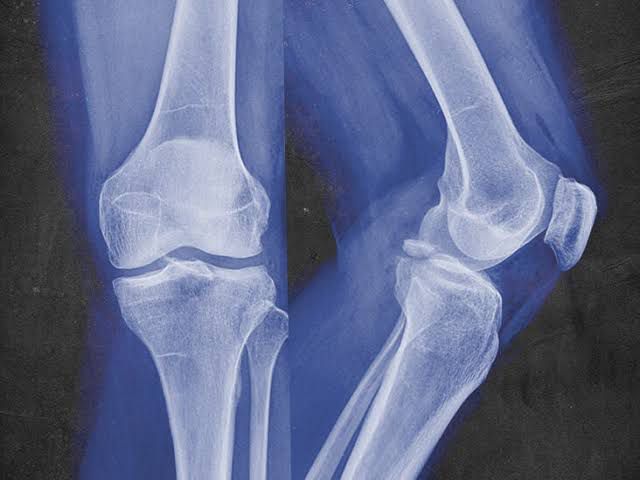

Playing sports comes with risks. Contact sports like lacrosse, boxing and football, for example, are the most common causes of avulsion fractures. It’s because contact sports involve movements that stress your limbs, such as: Suddenly changing direction. Sprinting. Kicking. Leaping. Falling on an outstretched hand. Suddenly accelerating (getting faster) or suddenly decelerating (going slower). Hitting, as in a boxer or a defensive lineman in a football game hitting an offensive lineman to protect the quarterback. Sliding, as in a baseball or softball player sliding into home base.